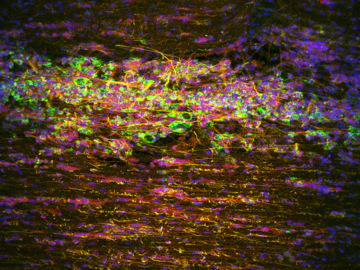

Striking Laboratory Data Images

Laboratory Data Gallery

Universe of the brain